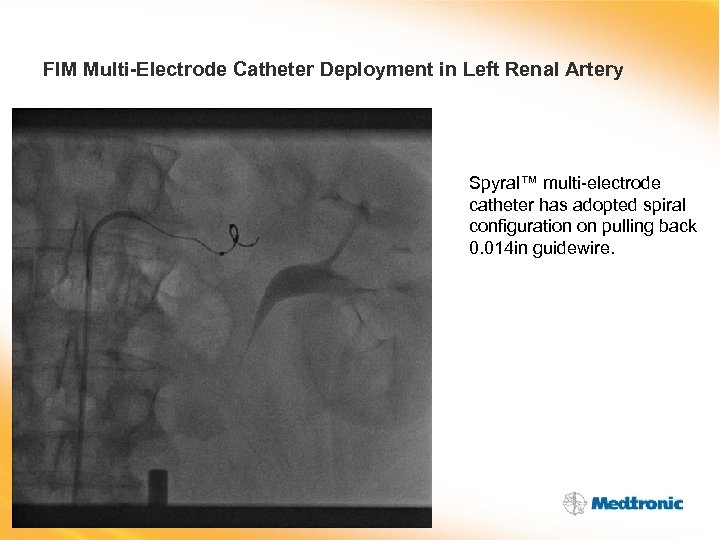

FIM Multi-Electrode Catheter Deployment in Left Renal Artery Spyral™ multi-electrode catheter has adopted spiral configuration on pulling back 0. 014 in guidewire.

FIM Multi-Electrode Catheter Deployment in Left Renal Artery Spyral™ multi-electrode catheter has adopted spiral configuration on pulling back 0. 014 in guidewire.